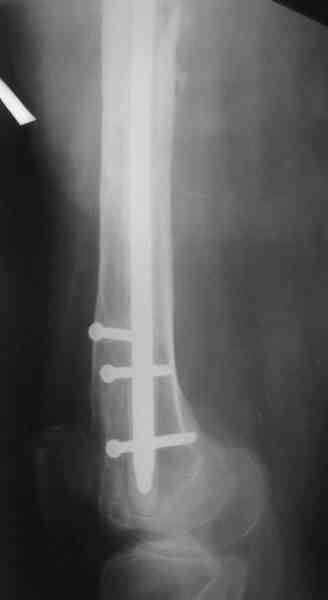

В настоящее время наш пациент ( см. http://weborto.net/forum/1177351385/) ходит с одним костылем. У него периодически открывается свищ на задне-наружной поверхности бедра с умеренным серозно-гнойным отделяемым. Температура тела и анализы нормальные. На рентгенограммах имеются признаки консолидации ложного сустава.

1, 2, 3, 4 - рентгенограммы бедра от 8 августа этого года (через четыре месяца после операции);

4, 5, 6 - рентгенограммы бедра и фотографии пациентки (прошу прощения за низкое качество рентгеновских снимков) от 7 сентября 2007 г.